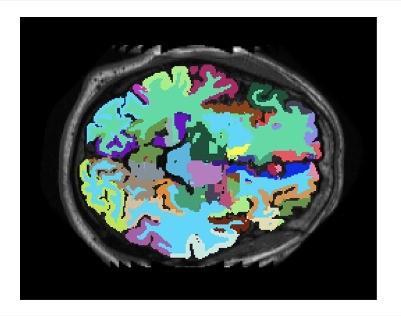

L’incontro si aprirà con l’introduzione del Prof. Franco Zambonelli, Vice-Rettore con delega al Dottorato di Ricerca ed Alta Formazione, che inquadrerà il ruolo sempre più centrale dell’IA nei processi di ricerca e innovazione. Seguiranno interventi di esperti Unimore attivi nei principali ambiti applicativi: il Prof Federico Bolelli del DIEF illustrerà le prospettive dell’intelligenza artificiale nel campo del medical imaging; il Prof. Giuseppe Boriani coordinatore del Dottorato di Ricerca in Clinical and Experimental Medicine e organizzatore dell'evento, approfondirà l’impatto dell’IA nei processi di decision-making e nella ricerca clinica e la Prof.ssa Elisa Ficarra del DIEF presenterà le applicazioni dell’intelligenza artificiale e della bioinformatica in ambito medico.